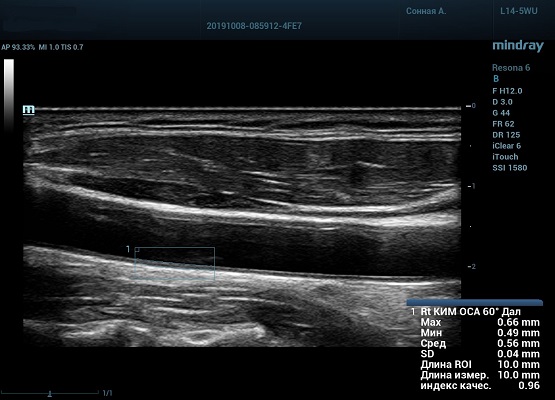

Также данный параметр используется для диагностики гипертензивной и атеросклеротической ангиопатии. Методика включает в себя измерение IMT проксимального, среднего и дистального отдела общей сонной артерии, каротидной луковицы, проксимального и среднего отдела внутренней сонной артерии. Далее вычисляем среднее значение и сравниванием с критериями Intima-mediathickness: Appropriate evaluation and proper measurement (ESC 2015, EAUD 2019) по центильной системе с привязкой к полу и возрасту.

На сегодняшний день измерение IMT происходит автоматическим путем при использовании функции AUTO-IMT. Необходимо указать прибору зону интереса, стандартной длиной (1 см), в которой происходит отслеживание кромок и выдача максимального, среднего и минимального значения.

УЗИ аппараты компании Mindray среднего, экспертного и премиального класса снабжены данной функцией и позволяют контролировать не только полученные значения, но и оценить точность измерения кромки в конкретной зоне по индексу качества. Используя индекс качества, легко решить, можно ли использовать полученное значение.